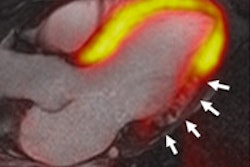

Image of CORE320 patient shows an occluded left anterior descending (LAD) stent on CT and catheterization, with the corresponding anterior wall defect demonstrated by CT perfusion and SPECT. Image courtesy of CORE320 investigators.The value of CT perfusion

Both invasive coronary angiography and CTA provide morphologic data, but they lack the physiologic information needed to determine the hemodynamic significance of a lesion. Proving that functional significance requires either catheter-based fractional flow reserve techniques, or noninvasive modalities such as SPECT myocardial perfusion imaging (MPI), PET, or MRI, the authors explained (Eur Heart J, November 19, 2013).